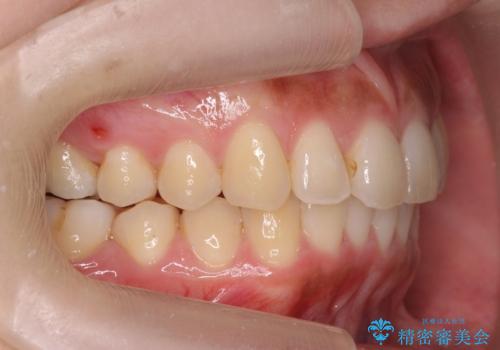

- 前歯のがたつきを主訴に来院。

前歯は目立つのでワイヤー矯正は絶対にしたくないとのことでした。

右上の奥歯を後ろに送り、前歯が出っ歯にならないように並べました。

また、右下の奥歯に一部目立たないように部分的なワイヤー矯正を行い、右下の奥歯が反対咬合になっていたのもしっかり中に入れて治療しています。

奥歯の反対咬合を治すのはインビザラインではかなり難しいのですが、しっかり治療できました。